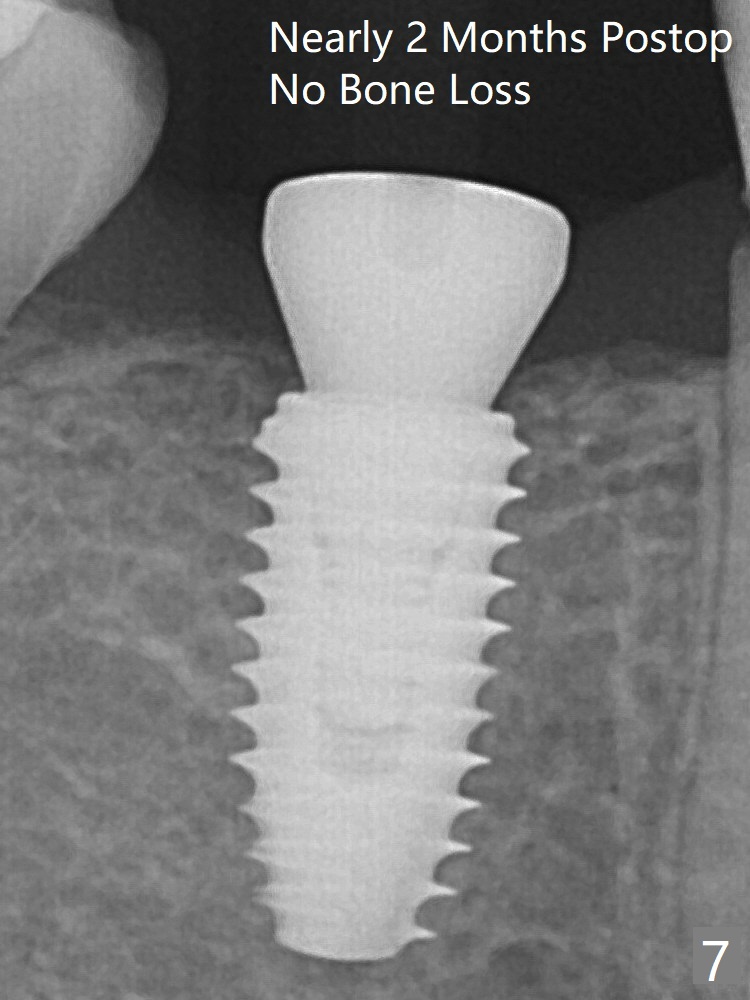

Everything happens so quick that when a 5.5x3 mm healing abutment is placed (Fig.4), you are pleased to feel that the implant is stable (Fig.5).  The patient returns for impression nearly 2 months postop (Fig.7,8).  It appears that the implant has osteointegrated without bone loss (Fig.7).  Guided surgery seems to be less traumatic than free hand one.  The soft tissue is healthy around the just placed cementation abutment (Fig.8 (5.2x4(2) mm).